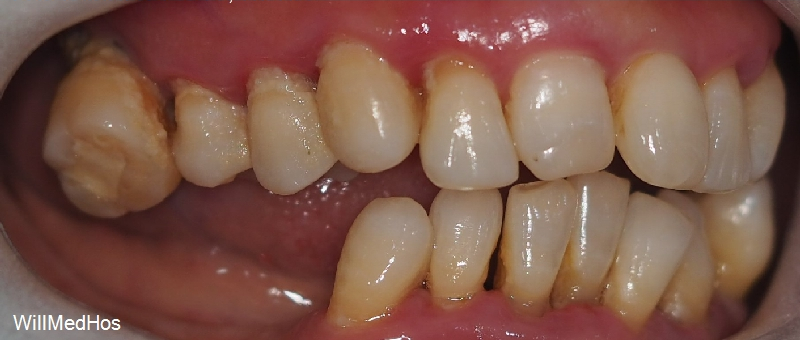

이미 자연 발치와 치과에서 발치 진단을 받으시고 발치 후 10년 가까이 치아들을

방치 해놓으신 상태라 위의 치아들이 정출되어 내려오기도 하고 관리가 아예 안되신 상태 이셨습니다.

상하악 전치부위와 소구치만으로 교합력을 견디기 어렵습니다.

이 교합 상태에서는 어금니가 수직 압력을 담당해 저작 시 앞니를 보호하고, 앞니는 측방(옆으로) 움직임에서 어금니를 보호하여 서로의 부담을 줄여 줍니다. 상호 보호 교합은 치아 마모와 턱관절에 가해지는 부담을 최소화하고, 안정적인 교합을 유지하는 데 중요한 역할을 합니다.

그런데 지금처럼 구치부가 모두 소실되어 교합이 무너지게 되면 전치부도 힘을 받게 되어 치조골이 소실됩니다 !!